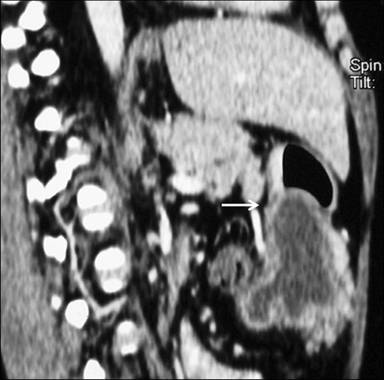

A 30-year-old woman presented with recurrent episodes of dull aching non-radiating abdominal pain of a 6 month duration which was localized in the epigastric region and was non colicky in nature with no relation to meals. It was associated with occasional non-bilious vomiting. There was no history of jaundice, gastrointestinal bleeding, melena, weight loss or altered bowel habits. There was no history of diabetes mellitus, tuberculosis, hypertension or cardiac disease. On examination, she was anicteric, had no pallor and no palpable lumps or tenderness. At admission, her hemoglobin was 11.9 g/dL (reference range: 12.0-14.0 g/dL), total leukocyte count 6,700 mm-3 (reference range: 4,000-9,000 mm-3), serum total bilirubin 0.6 mg/dL (reference range: 0.3-1.3 mg/dL), aspartate transaminase 18 IU/L (reference range: 7-41 IU/L), alanine transaminase 16 IU/L (reference range: 12-38 IU/L), alkaline phosphatase 201 IU/L (reference range: 80-290 IU/L), and serum amylase 112 IU/L (reference range: 22-80 IU/L). A contrast-enhanced CT scan showed a cystic lesion with finger-like projections abutting the pylorus and the antrum of the stomach with an adjacent stippled fat density lesion (Figures 1 and 2). Ultrasound of the abdomen showed an anechoic cystic structure with an inner hyperechoic layer and an outer hypoechoic layer which was contiguous with the muscle layer of the stomach (Figure 3), confirming the diagnosis of a duplication cyst.

Figure 1. Contrast-enhanced CT (sagittal multiplanar reconstruction) of the abdomen shows a hypodense cystic lesion indenting the stomach wall (arrow). Finger-like projections are seen along the inferior aspect of the cyst. |